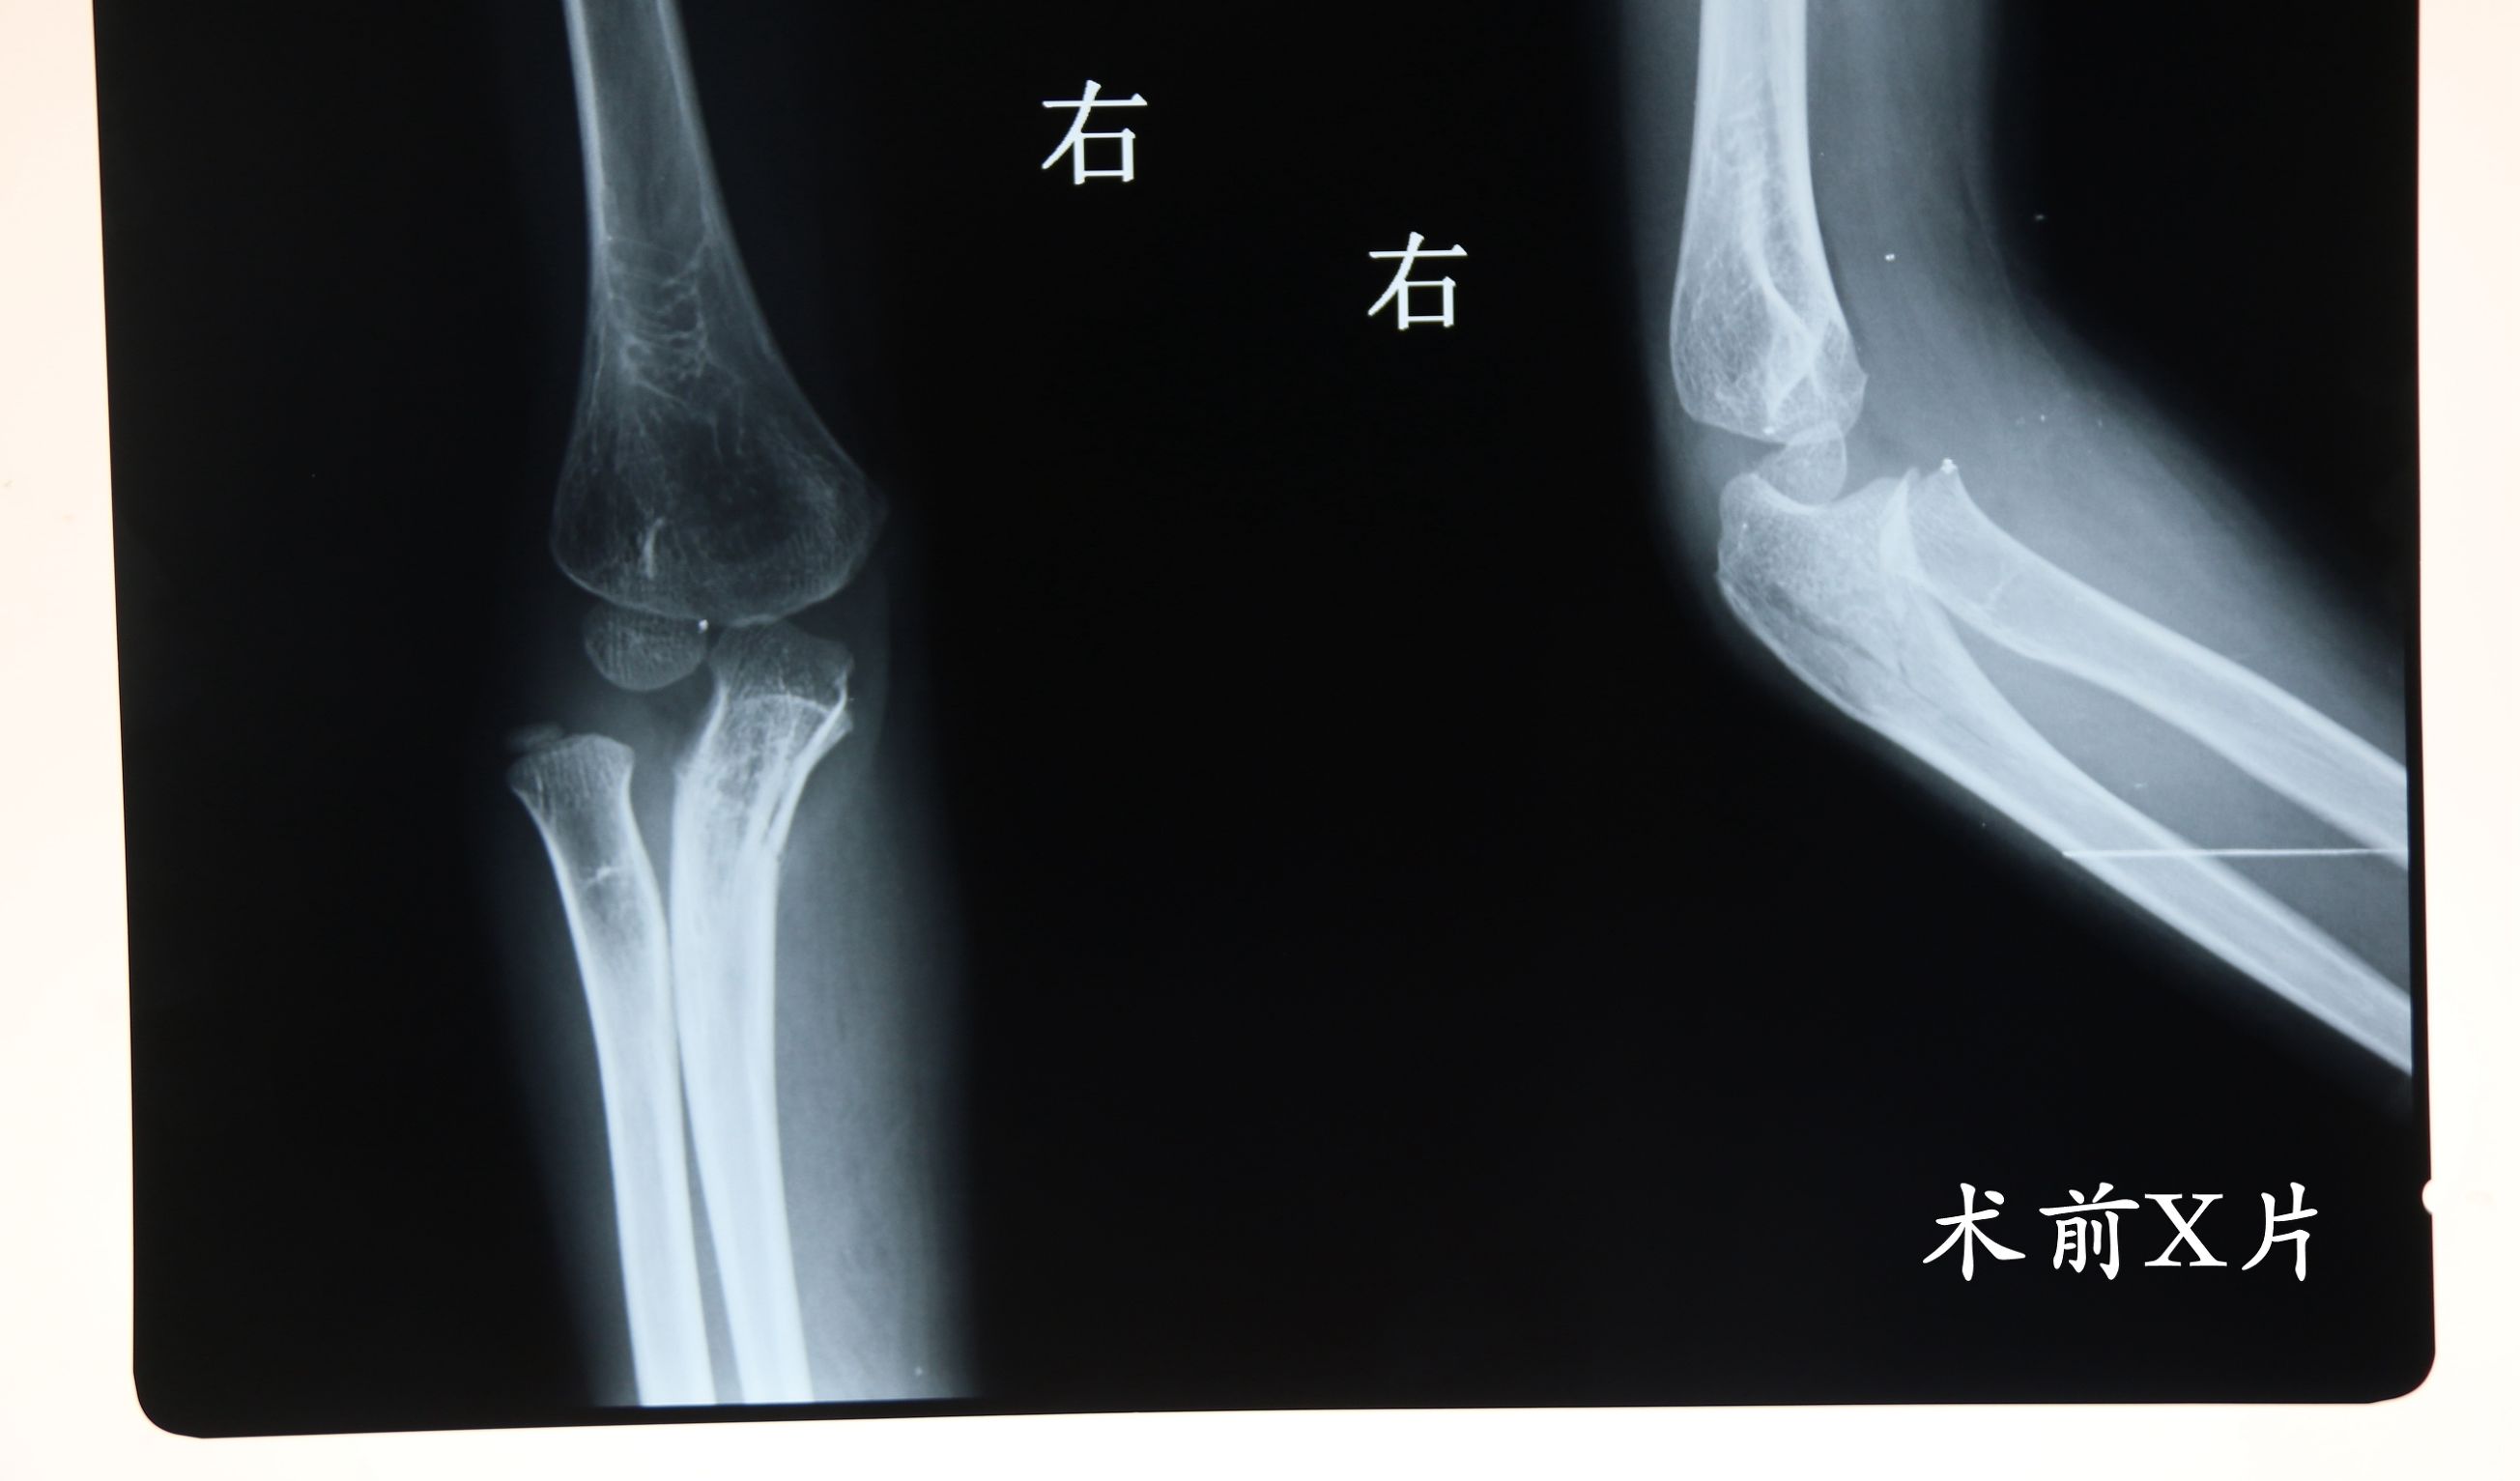

孟氏骨折有4种类型,其中Ⅲ型孟氏骨折只见于儿童,是由伸肘位摔倒,上肢处于内收位,肘关节受到内翻应力,是尺骨上端发生桡侧成角的骨折,桡骨头向外侧脱位导致的。

儿童骨折中有那么多类型,要如何才能诊断它就是孟氏骨折呢?孟氏骨折在受伤后肘部及前臂肿胀,移位明显者可见尺骨成角或凹陷畸形。肘关节前外或后方可摸到突出的挠骨头。前臂旋转受限。肿胀严重摸不清者,局部压痛明显。家长可在孩子发生骨折时为孩子做以上简单的查体工作,但若要精准的判断和治疗,还需要医生的专业诊断和使用相应的医学设备辅助检查。

当保守治疗不能达到预期效果时,则采用手术治疗。手术治疗主要是采用固定尺骨的方法使桡骨头维持复位。主要采用克氏针、弹性髓内针、钢板的方法固定尺骨,长臂石膏托外固定,前臂固定于桡骨头最稳定的位置。术后3~7天拍片复查,术后3~4周去除外固定。

对于漏诊的陈旧性孟氏骨折则采用切开复位内固定手术。主要采用克氏针、外固定架、钢板。如尺骨有成角或尺骨短缩,还需行尺骨截骨。术后石膏固定3~4周。